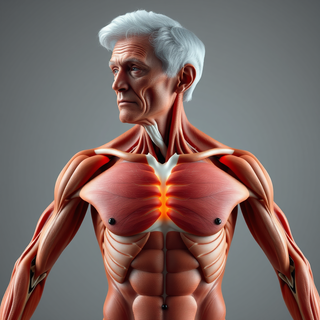

Generate ultra-realistic microscopic imagery for medical research.Open

Generate ultra-realistic microscopic imagery for medical research.Open